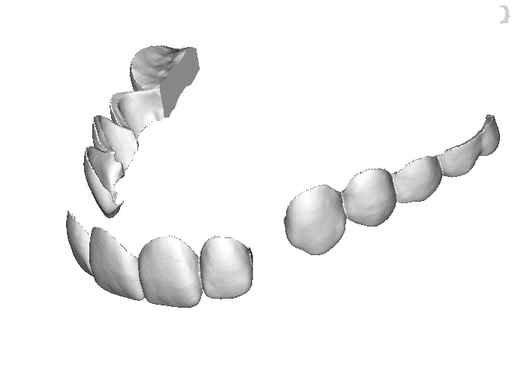

The DSD Interdisciplinary is a digital wax up of the upper and lower arches, designed considering a facially-driven, clinical and functional analysis of the patient.

It is our most comprehensive planning option, and includes all the 3D treatment simulations needed for each case, such as ortho, perio, implants, grafts and orthognathic surgery.

Our 3D simulations showcase various treatment suggestions, facilitating a deeper understanding of the required procedures. This leads to the creation of a broader treatment plan and enables a more efficient communication with your patients.